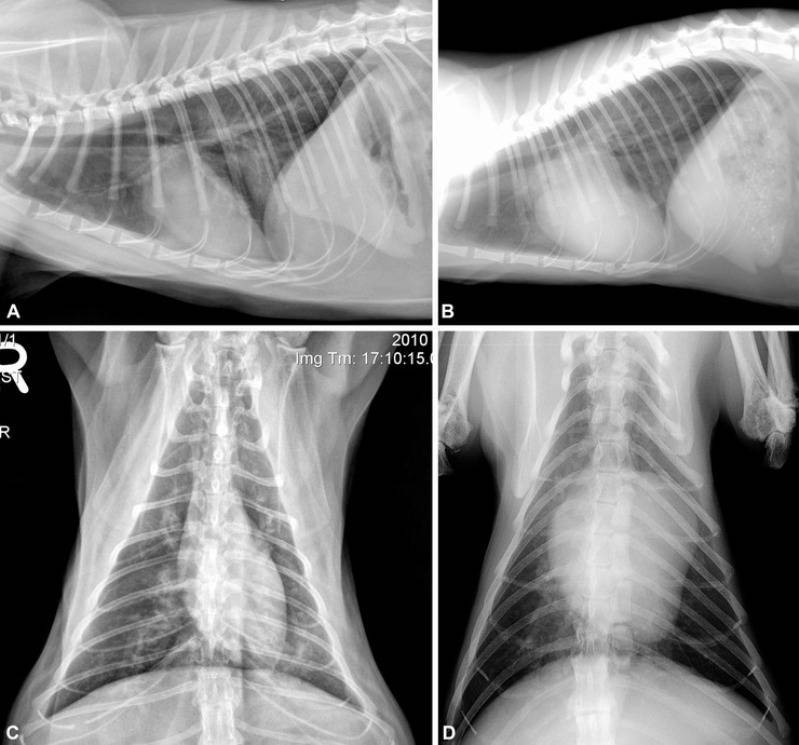

В клинике собаке сделают рентген, который подтвердит или опровергнет отек легких, а также проведут осмотр собаки, прослушают ее и выполнят ряд лабораторных исследований.

Для диагностики отека легких у собак используются такие методы, как аускультация, рентгенография грудной клетки или ультразвуковое исследование, также требуется анализ крови. Электрокардиограмма, анализ мочи и измерение кровяного давления — другие важные тесты, позволяющие выяснить, есть ли у вашей собаки отек легких.

Если состояние вашего питомца стабильное, можно выполнить рентгенографию грудной клетки, положив собаку на спину. На этой рентгенограмме могут быть признаки отека легких, такие как повышенная интерстициальная или альвеолярная непрозрачность. У собак, страдающих кардиогенным отеком легких, также могут наблюдаться кардиомегалия и расширенные легочные вены.

Рентгеновские снимки являются основным инструментом для диагностики отека легких, поскольку они выявляют жидкость внутри легких собаки. Рентген также может выявить увеличенное сердце или другие аномалии сердечной мышцы.